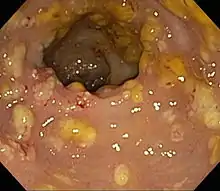

While there have been no reports of severe organ toxicity from lincosamide treatment, gastrointestinal disturbances have been associated with their administration. Pseudomembranous enterocolitis resulting from clindamycin-induced disruption of gastrointestinal flora can be a lethal adverse event observed in several species when used in the veterinary clinic, particularly in horses. At extremely high doses of clindamycin, skeletal muscle paralysis has been demonstrated in several species. Lincosamides can interact with anesthetic agents to produce neuromuscular effects.[28]